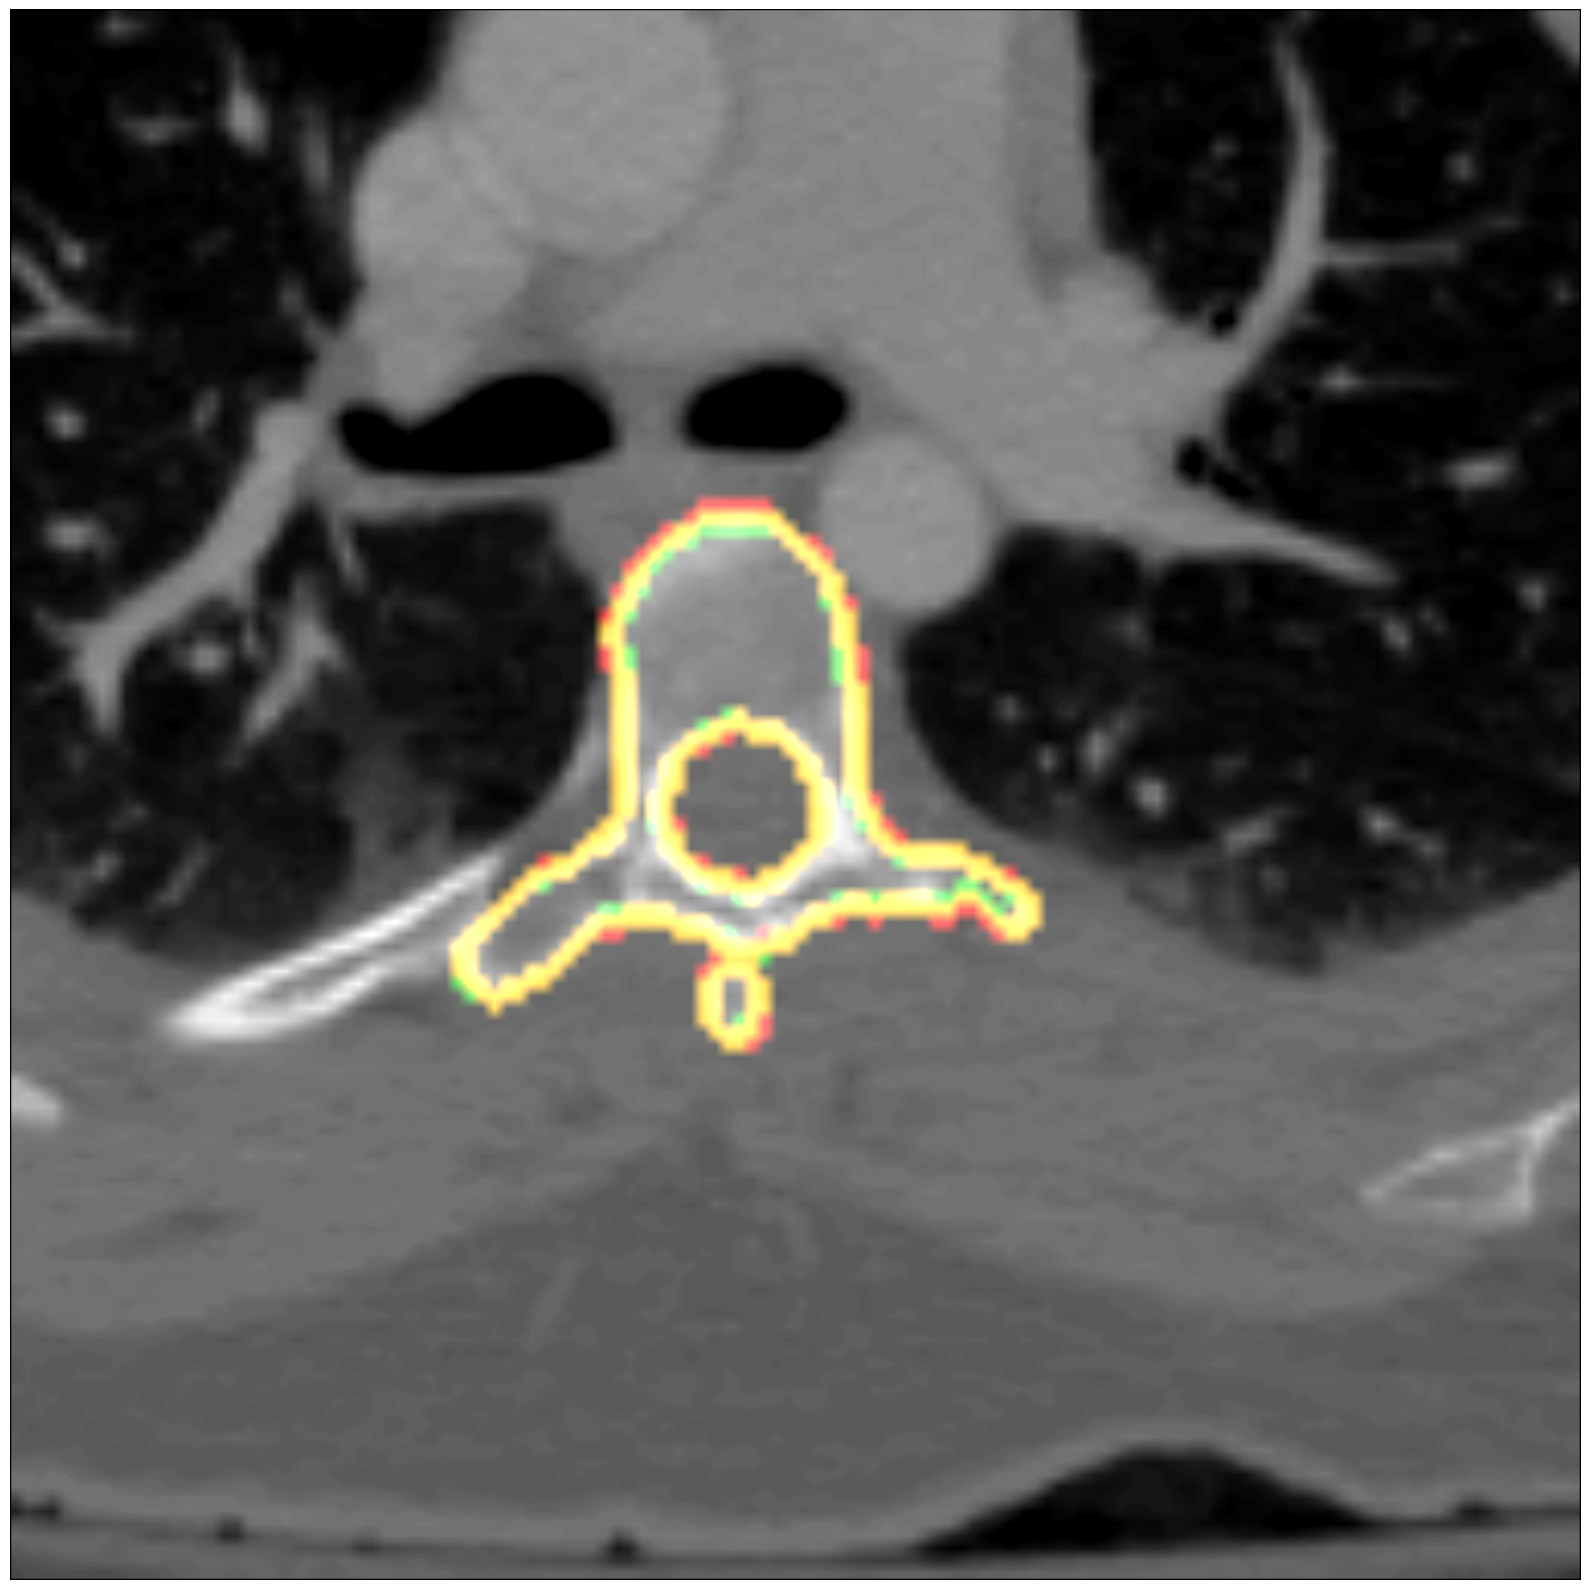

Some segmentation results at different vertebrae (top) and liver (bottom) areas are depicted in Fig. 2. The red contour corresponds to the outline of the prediction, green to the ground-truth and yellow to the overlap of the outlines.